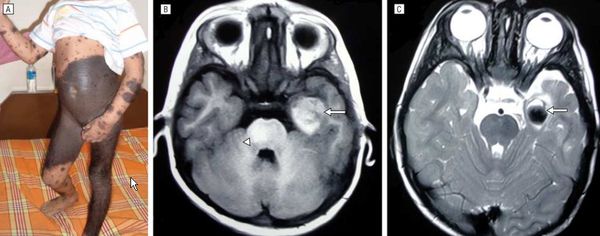

Очаги поражения в виде односторонних гигантских бляшек эпидермального невуса располагаются линейно, в виде гирлянд в сочетании с различными системными аномалиями (кисты и гипоплазия костей, сколиоз, позвоночные расщелины, кифоз, умственную отсталость, эпилепсия, дисгенез структур головного мозга, гидроцефалия, микроцефалия, катаракта).

При подозрении на синдром эпидермального невуса применяют КТ /МРТ, офтальмологическое исследование, электроэнцефалографию, рентгенографию скелета.

Нейрокожный меланоз

В редких случаях развивается нейрокожный меланоз — заболевание, при котором меланоциты разрастаются в центральной нервной системе. К таким нарушениям может приводить мутация гена BRAF [50] .

![Нейрокожный меланоз]()

Факторы риска развития нейрокожного меланоза:

- гигантский невус на спине (более 40 см);

- множественные невусы-спутники — чем их больше, тем выше риск;

- более двух средних невусов, особенно если помимо них много других невусов.

Болезнь тяжелее переносят дети младше 10 лет.

В исследовании американских учёных меланоз диагностировали у 26 из 379 пациентов с большими врождёнными невусами [12] . Заболевание может протекать без симптомов и случайно выявляться при МРТ, но в некоторых случаях оно сопровождается неврологическими нарушениями:

Неврологические симптомы могут развиться из-за кровоизлияния в желудочки головного мозга, нарушения циркуляции спинномозговой жидкости, сдавления спинного мозга или злокачественного перерождения меланоцитов [3] [14] .

Симптомы появляются примерно в двухлетнем возрасте. Прогноз чаще неблагоприятный, даже если нет злокачественных новообразований [15] . В одном обзоре были изучены 39 случаев симптоматического нейрокожного меланоза: более половины пациентов погибли в течение трёх лет после появления неврологических нарушений [34] .